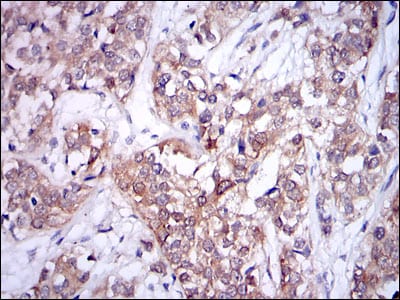

Immunohistochemical analysis of paraffin-embedded human prostate tissues using UBE2I mouse mAb with DAB staining.

Immunohistochemical analysis of paraffin-embedded human bladder cancer tissues using UBE2I mouse mAb with DAB staining.